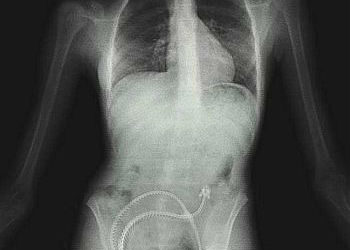

El gráfico